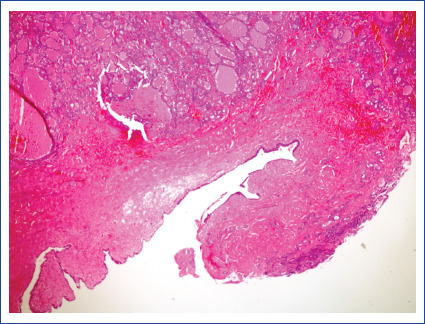

Abstract Image